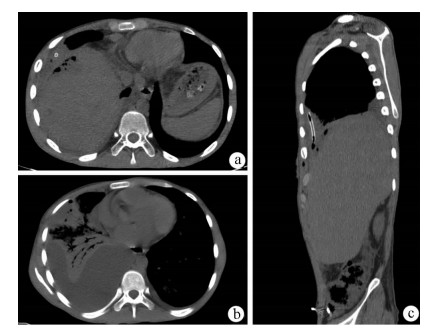

Jaundice and portal hypertension caused by hepatic epithelioid hemangioendothelioma: A case report

Ruihua ZHANG, Tingting QIN, Yueming SHAO, Yu ZHANG, Yang WANG, Xiaoyu WEN

2021, 37(7): 1662-1664. DOI: 10.3969/j.issn.1001-5256.2021.07.036

Abstract(984) HTML (197) PDF (2873KB)(66)

Abstract: